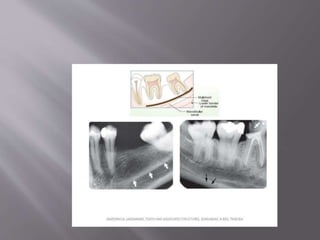

 Expansion of sinus is larger following multiple

posterior teeth extraction

 For placement of dental implant in such cases

immediate implant and/or immediate bone

grafting should be considered to assist in

preserving 3-D architecture of the sinus floor at

the extraction site